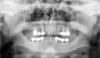

Budovsky Alexander Опубликовано 14 июля, 2010 Поделиться Опубликовано 14 июля, 2010 Реконструктивное протезирование цельноциркониевыми конструкциями.Пациент обратился ко мне со следующей проблемой. После консультации пациент лечился в другой клинике. Где ему были удалены пластинчатые имплантаты, установлены 6 Replace, пролечены зубы, выбит 26 и вывихнут 25. Через несколько месяцев обратился ко мне снова.Орто, видимо, на этапе имплантации.Очень сложный и интересный случай.Обратите, пожалуйста внимание – сильная стираемость передней группы зубов. При этом высота коронковой части зубов в боковом отделе была долгое время сохранена на мостовидных протезах и пластинчатых имплантатах. Т.е., стирался только фронт. Можно представить себе какой тип движения сформировался в суставе. Также произошло сильное снижение прикуса. Но из-за подобного типа протетики, а также большой убыли костной ткани после удаления имплантатов в дистальном участке сформировалась большая дизокклюзия. Посмотрите на орто ещё раз. Прикус разобщён, и на каком расстоянии находятся жевательные поверхности металлокерамических коронок.Я довольно подробно изучил зубочелюстной аппарат данного пациента. Т.к., в литературе такой тип стираемости описывается у австралийских аборигенов, как хеликоидальный с переходной зоной в области 2 моляров. Но в данном случае не была, по всей видимости, создана сагиттальная компенсационная кривая (Шпее). Что и привело к стиранию резцов при протрузионном движении и формированию серьёзного разобщения в области боковых зубов. Прежде чем что-то делать с пациентом, я провёл подробную диагностику и моделирование в программе и воске. Анализ ТРГ показал сильное снижение высоты прикуса на 11 градусов - угол ANSXiPM 32° Lower facial height , нейтральное положение верхней челюсти, несколько дистальное положение нижней челюсти. Что есть нехорошо, т.к., при повышении прикуса произойдёт ещё большая дистализация нижней челюсти. А поднимать надо прилично. Это, в свою очередь, может привести к «задавливанию» биламинарной зоны сустава и пациент может не адаптироваться.Расчёт по Ricketts:variable value norm value deviation descriptionNBaPtG 101° 90±3° +8 Facial axisNPogPOr 86° 87±3° 0 Facial depthMeGoPOr 16° 26±6° -4 Mandibular planeANSXiPM 32° 47±4° -11 Lower facial heightDCXiPM 43° 26±4° +13 Mandibular arcA-NPog -1mm 2±2mm -1 Convexity1l-APog -2mm 1±2mm -1 distance of incisal edge of 1l to A-PogMand1-APog 27° 22±4° +1 angle of axis of 1l to A-Pog6uPTV 22mm 12±3mm +7 distance of distal outline of 6u to PTVLi-NsPog' -8mm -2±2mm -4 distance of lower lip to esthetic lineMeGoNPog 78° 68±4° +7 Facial taper При краниометрии по Шварцу выяснилось, что у пациента дополнительно инфрапозиция ВНЧС ( угол Н 93 градуса), смещение верхней челюсти дистально в сагиттальной плоскости ( фациальный угол 81), косое смещение зубочелюстного комплекса кзади – скошенный костный профиль дистально ( угол инклинации составил 81). Профилометрический угол Т 4 градуса, что на 6 градусов меньше нормы нейтрального профиля. Но в данном случае, выступание мягкотканного профиля компенсирует скашивание костного профиля кзади и дистальное положение нижней челюсти. Возникает делема. Повышение прикуса необходимо по всем признакам, в первую очередь по эстетическим. Но это может ухудшить профиль и сдвинуть нижнюю челюсть кзади, что явится причиной дисфункции. variable value norm value deviation descriptionF 81° 85° -4 facial angleH 93° 90° +3 H-angleI 81° 85° -4 inclination angleT 4° 10° -6 profile angleProf anterior divergent profileType posterior face facial type Учитывая эти данные, надо проявлять большую осторожность при протезировании, особенно при повышении прикуса. Далее, я провёл симмуляцию клинического случая в программе и восковое диагностическое моделирование. Ссылка на комментарий

Budovsky Alexander Опубликовано 16 июля, 2010 Автор Поделиться Опубликовано 16 июля, 2010 После получения всех необходимых данных и настройки артикулятора, я приступил к восковому моделированию. Моделировку, в основном, я делал по Зойберу, с применением окклюзионного компаса. Но также, попробовал и по другим авторам А. Кнаус, Штегер,Славичек,Симон Хауг. Очень рекомендую, в этом смысле, монографию Зойбера,прекрасная книга,но когда нет антагонистов, надо строить несколько иначе. Мне пришлось несколько раз перемоделировать. Формирование восковых конусов позволяет видеть общую картину, высоту и размер зубов, симметрию рядов и сторон. Поэтому много разноцветного воска. Уже на стадии моделировки резцов становится понятно, что у пациента не только глубокий прикус,но и глубокое резцовое перекрытие.http://s60.radikal.ru/i167/1007/38/30f711db7fe0t.jpgОбратите внимание,что с повышением прикуса меняется ось наклона резцов. Жёлтый гипс - направление своих зубов, воск - уже новое положение. Вы должны это понимать на стадии планирования работы. Т.к., например, культевые вкладки Вам сделают по направлению оси зуба. Большинство антагонистов стоят "зуб в зуб". Т.е., по 2 классу, соотношение 1 к 1.http://i058.radikal.ru/1007/82/9d5d2749978et.jpgС правой стороны на верхней челюсти два премоляра не помещаются. Получится один, но побольше. Справа внизу имплантат стоит на некотором удалении от 44, поэтому лучше моделировать молярhttp://s58.radikal.ru/i161/1007/2e/e2952baa2ff6t.jpg Слева - не легче.http://s47.radikal.ru/i115/1007/d1/ff1080a1c1eb.jpg Имплантаты стоят слишком далеко от 33 и слишком близко друг к другу. На 36 - 2 имплантата, на 34 и 35 - один. При этом два премоляра с трудом туда влезают, тесня друг друга.http://s39.radikal.ru/i086/1007/8f/6a6d21711ea0t.jpghttp://s43.radikal.ru/i102/1007/cf/0b505be6124at.jpg 26 восстановлен мной полностью из воска, для получения ориентиров при моделировке 36. Фронт - http://s16.radikal.ru/i190/1007/09/833ff90d50ba.jpg Не совпадение средних линий, уровень десневого края на разной высоте, расстояние зубов на левой и правой стороне от средней линии разное, также как и геометрические размеры зубов.http://s57.radikal.ru/i156/1007/0f/d02dedc75031t.jpg При моделировке нёбной поверхности, мы видимhttp://i078.radikal.ru/1007/34/c90393a4ab86t.jpg что произошло смещение нижней челюсти влево, антагонисты и в трансверзальной плоскости стоят не симметрично. Особенно нехорошо попадание нижнего правого клыка прямо в центр нёбной поверхности 13. Это затруднит формирование клыкового ведения, места на нёбной поверхности коронки будет недостаточно. На стадии диагностики делается полностью разборная модель нижней челюсти. Это позволяет моделировать каждый зуб отдельно и отрабатывать его боковые движения. В противном случае, всё будет разводить клык.http://i061.radikal.ru/1007/22/4aa7ddc703cdt.jpg Итак, у пациента глубокий прикус, осложнённый глубоким резцовым перекрытием. Десневой край резцов и клыков находится на разном уровне. Зубы левой и правой сторон имеют различные геометрические размеры и пространственно расположены несимметрично. Имплантаты стоят не в области отсутствующих зубов, а своеобразно, и имеют приличный наклон. Оси альвеолярных гребней верхней и нижней челюсти расходятся, присутствуе зубоальвеолярная компенсация. Это краткая гнатометрическая характеристика на основании воскового диагностического моделирования.. Обычно все эти крокодилы всплывают на керамике. Начинать надо с диагностики и дальше уже планировать всю работу. Тогда всё и все будет по местам. Ссылка на комментарий